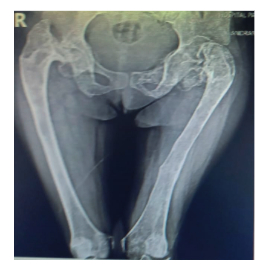

Figure 2. Hip and AP radiograph of bilateral femur: an inveterate fracture is evident at the level of the left femoral neck in addition to bilateral coxa vara.

Figure 3. Lateral radiograph of the left femur: poor bone quality, very thin cortices, ground-glass images, areas of osteolysis and osteosclerosis in the greater and lesser trochanters and the neck of the femur, loss of distinction between the cortex and the bone marrow of the upper part of the femur.